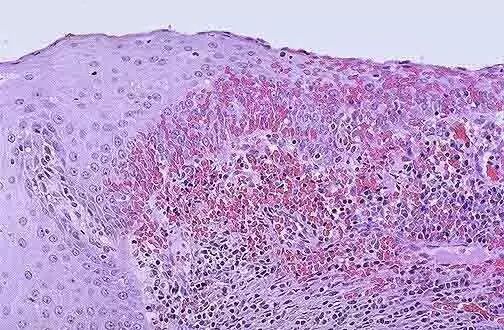

免疫检查点是机体免疫体系中的抑制性通路。它在维持自身免疫耐受、调控生理性免疫应答中发挥着重要的作用,此外,也促进了肿瘤细胞的免疫逃逸。免疫检查点抑制剂(ICIs)则可以特异性针对阻断某一免疫检查点的信号通路,以此改变肿瘤的微环境,破坏肿瘤细胞。

近年来,肠道菌群与肿瘤的免疫治疗的相关研究取得了极大的进展,尤其是在黑色素瘤的研究中。Sivan等选用了两种拥有不同肠道菌群的同一种系小鼠,观察二者黑色素瘤的生长情况。研究初期,由于两种小鼠拥有不同肠道菌群,二者体内产生的T细胞免疫应答不同

1、主要表现为肿瘤特异性CD8+T细胞的反应强度的不同,最终黑色素瘤的生长速度也不同

2、将它们同笼饲养或进行粪菌移植后,肿瘤的生长速度则趋于一致。

这表明,肠道菌群的差异导致了肿瘤的生长速度的不同。

对它们粪便菌群的丰度进行比较后发现,有活性的双歧杆菌如短双歧杆菌、长双歧杆菌和青春双歧杆菌在抗肿瘤中起到了重要作用。

同时研究发现双歧杆菌是通过与树突状细胞相互作用,激活T细胞,促进抗肿瘤免疫反应。

口服双歧杆菌可以增强针对PD-1/PDL-1的ICIs的抗肿瘤作用,而两者同时使用后几乎可完全抑制肿瘤的生长。